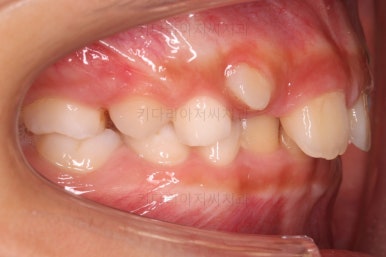

마찬가지로 초진시의 입안 모습입니다.

보호자분 말씀처럼 윗니가 아랫니에 비해서 나와보이는게 사실이네요.

이번 환자분의 경우 골격 자체가 위턱(코주위~윗니부분을 아우르는 골격)이 약간 앞으로 발달하고 아래턱이 성장이 모자라 뒤로 들어간 상태였어요.

따라서 상대적으로 위턱이 크고 상대적으로 아래턱이 작았던거죠.

이런 부조화된 모습때문에 입을 어색하게 다물게 하고 입을 튀어나와 보이게 만드는거였어요.

이번 환자분은 무턱 + 돌출입 성장교정이 목표였지만 그전에 치아의 맹출경로가 엉켜서(화살표) 치아의 손상 혹은 매복치아의 우려가 있는 부분을 먼저 개선하기로 했습니다.